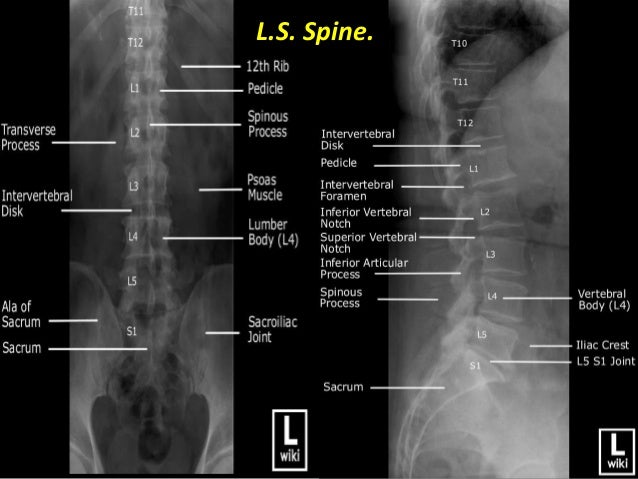

Presentation1.pptx, Normal Spinal Anatomy.

Presentation1.pptx, normal spinal anatomy. www.slideshare.net

spinal spine foramen presentation1 sacral articular pptx